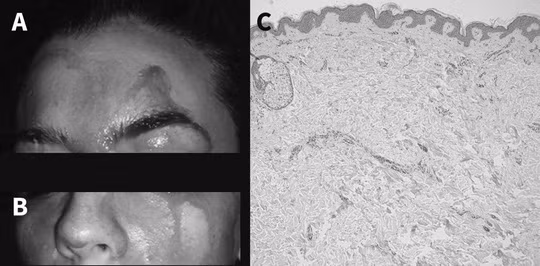

Nữ bệnh nhân với khuôn mặt thường xuyên ướt đẫm máu - ảnh do nhóm nghiên cứu cung cấp. |